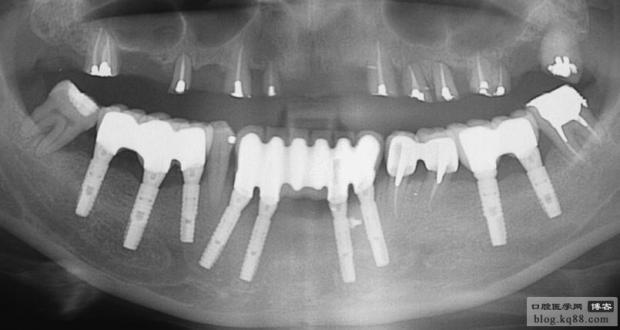

上頜是保留殘根覆蓋義齒,下頜是種植修復(fù),仔細(xì)看左上3側(cè)支根管被根充